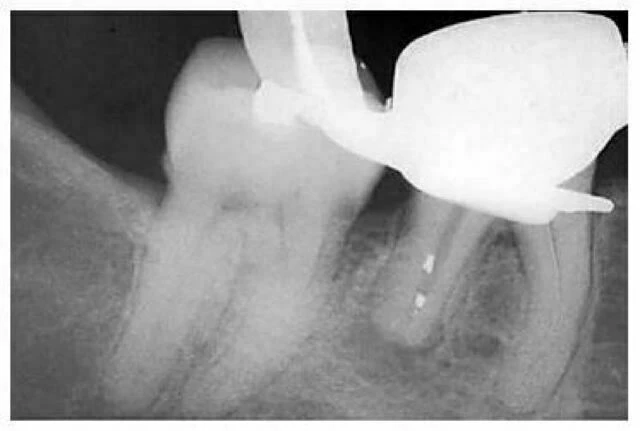

Để tránh những mảnh ngà vụn, hoặc amalgam hoặc những vật liệu trám khác rơi vào xoang hay ống tủy đã được làm sạch và tạo hình, ta nên đặt một cục bông nhỏ ở xoang (hình 11.8). Một nguyên tắc không thể quên đó là: ta nên sửa soạn một xoang tủy rộng và lấy bỏ miếng trám kim loại rộng rãi để tránh phải mở rộng xoang lần nữa trong lúc đang sửa soạn ống tủy vì nếu lúc này dùng tay khoan thì nước sẽ đẩy chất bẩn vào trong ống tủy.

Hình 11.8. Một xoang tủy được mở qua một mão răng ở phía gần sau khi ống xa đã được sửa soạn. Nước xịt từ tay khoan siêu tốc làm chất trám kim loại rơi vào ống tủy chân xa.